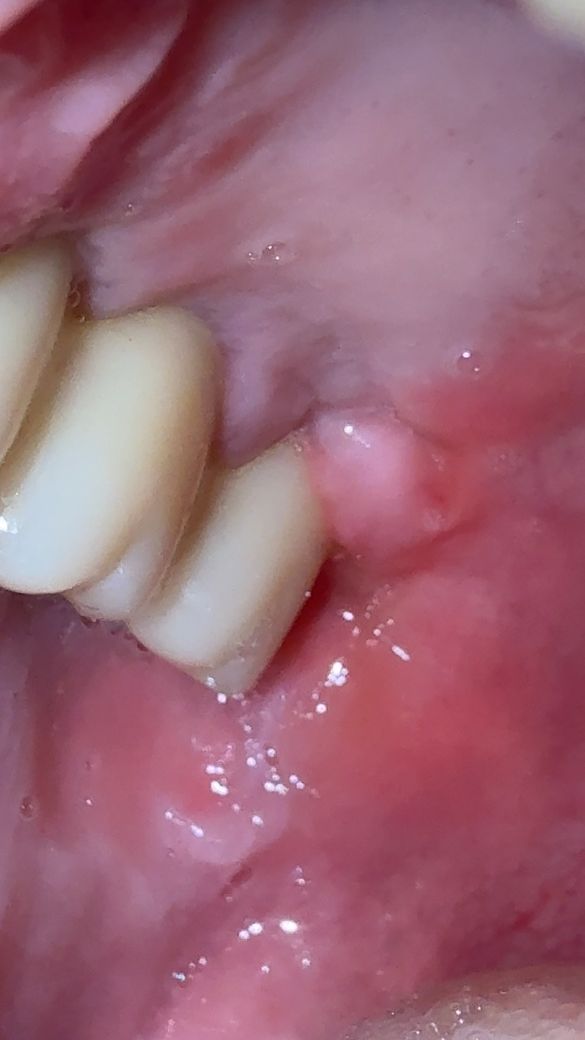

첫번째 사진은 어제아침 기상 후 불편감에 찍어본 사진인데 끄트머리 잇몸이 많이 부풀어있는듯하여

• 1번 째 사진